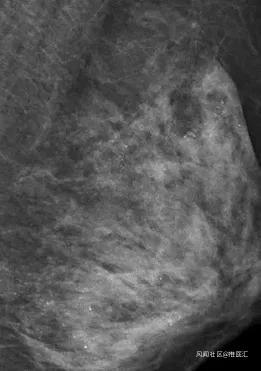

乳腺外科

討厭亂貼膏藥的、相信精油按摩能治好乳腺腫物的……

常年做胸部精油推拿,結果按出了“砂粒胸”,只能切乳房保命。